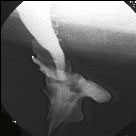

Prolasso

intracanalicolare breve con ristagno di barite a monte.

Il serbatoio ampollare

assume aspetto a "scodella" |